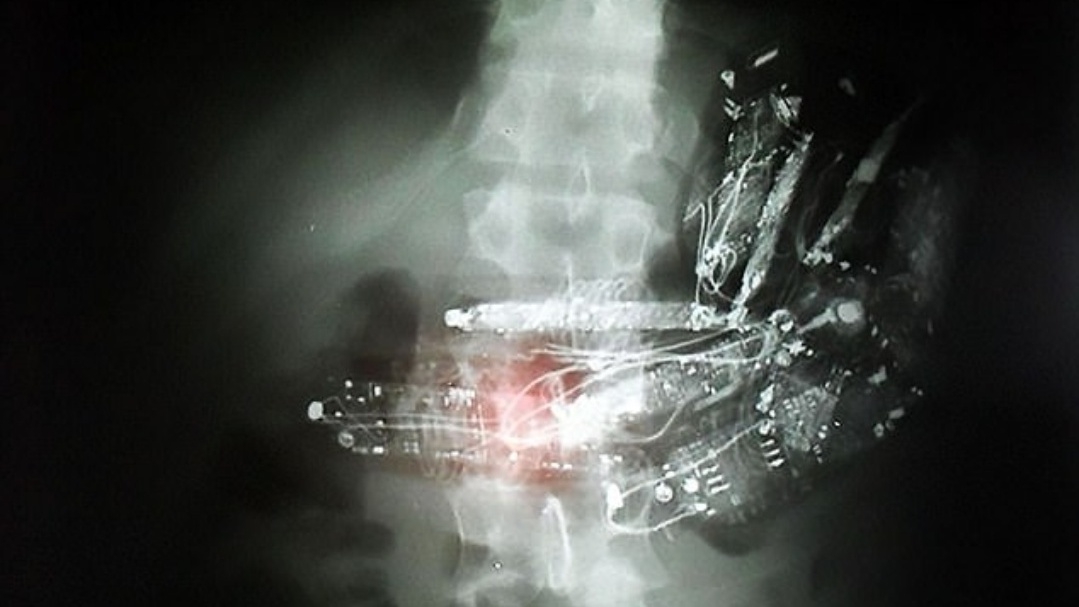

โดยการตรวจพบในครั้งนี้ เกิดขึ้นภายหลังจากมีการติดตั้งเครื่องตรวจโลหะภายในเรือนจำแห่งหนึ่งในเมืองเซาเปาโล จนกระทั่งนำไปสู่การจับนักโทษที่เข้าข่ายน่าสงสัย เข้าไปตรวจด้วยฟิล์มเอกซเรย์ จนกระทั่งพบเรื่องที่น่าตกตะลึงขึ้น และล่าสุดขณะนี้ได้มีการสั่งให้มีการสอบสวนหาข้อเท็จจริงในเรื่องที่เกิดขึ้นทั้งหมดแล้ว

โดยหลังจากถูกจับได้ มีรายงานว่า นักโทษที่กลืนโทรศัพท์มือถือลงไปในท้องถึง 10 เครื่อง ต้องถูกนำตัวไปผ่าตัดเพื่อนำสิ่งแปลกปลอมออกมาทั้งหมด ส่วนอีก 2 คนที่เหลืออาการไม่ได้น่าวิตกแต่อย่างใด